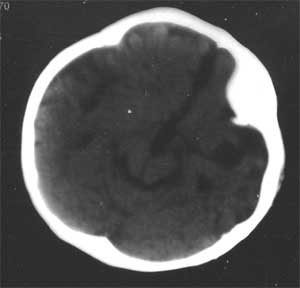

幕上幕下脑室、脑池、脑沟均见扩张积液,考虑脑发育不良。片子质量不好,前囟门似乎偏小,颅骨骨缝不知是否有闭合。9个月幼儿,头围应该不小于40厘米,请测量头围周径。应该没有胼胝体发育不良。至于“右侧基底节区缺血性改变”,片子质量差,看不清楚。

粗看:1。双侧额颞顶叶均有不同程度萎缩,脑实质变薄,2。脑室系统对称性扩张,大脑沟裂增宽变深。3。双基底节区未见明确低密灶,胼胝体发育良好。综上所述考虑有:1)大脑发育不良;2)严重脑缺血缺氧性脑病后遗症?个人意见仅供参考。

患儿脑发育不良,颅板增厚,不应是缺血缺氧性脑病后遗改变,应为先天异常,可查一下染色体。绝大多数脑瘫、低能儿都有颅板增厚。

脑容量不够,脑沟裂增深增宽,脑室系统扩大。片子质量有问题,暂考虑:以脑发育不全为首诊。

大脑腔室较大,脑沟宽,应该考虑大脑发育不全或脑萎缩

脑组织容积总体来说是欠一点,且脑沟宽,脑室大,所以脑白质为主发育不良或迟缓是可以肯定的,因为症状亦有,但基底节低密病及胼胝体异常肯定没有,因为ct片是不太好.[emb21][emb21][emb21]